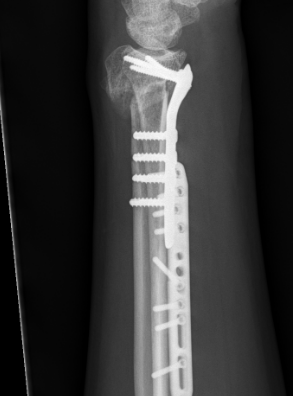

Xray

Bilateral xrays

PA film in neutral

- wrist neutral

- elbow & shoulder at 90°

CT

Ulna shortening

Radial osteotomy - volar versus dorsal

Radial osteotomy + ulna shortening +/- distal ulna resection / fusion

Ulnar Shortening

Indications

Short radius, positive ulna variance

Acceptable alignment distal radius

Acceptable DRUJ

Technique

Approach to ulna

- between ECU and FCU

- can use cutting jigs

- resect 2 - 6 mm of ulna based on xray templating

- compression plate

Distal radial osteotomy

Dorsal tilt / radial tilt / loss of inclination

Acceptable DRUJ articular surface

Dorsal opening wedge osteotomy

Advantage

Lengthens the distal radius

May be easier to correct in coronal and sagittal plane

Disadvantage

Dorsal approach / dorsal plate - extensor tendon issues

3 / 4 dorsal approach

- expose distal radius

- can use half pins to control distal fragment

- protect structures with homan retractors

- osteotomy with microsagittal saw

- correct radial articular surface in sagittal & coronal planes

- trapezoidal bi-cortical iliac crest autograft / synthetic graft

- dorsal locking plate